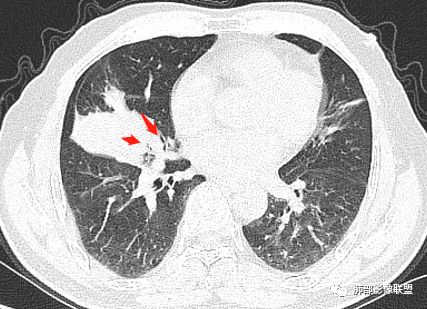

我来抛砖引玉:

空气储留,支气管炎

管辖的支气管是壁增厚,狭窄的

它不是只有一支支气管有问题,而是多支

这个是上叶支气管,而且一般慢性炎症更容易空气储留,因为是缓慢的才会气体易进难出。

主病灶在中叶,但是左肺舌段叶有条索影,陈旧病变。蓝色箭头支气管受压,是淋巴结肿大

主病灶在中叶,但是还有结节状病变在下叶

是这样长过去的吗?

叶间裂推移方向

虽然是一个大的病灶,但是周围是比较散

这个支气管是走形通畅,但是壁增厚的。比较符合炎症改变

下面我们看看支气管都在吗?

内侧段是通畅但是受压的

外侧段一开始狭窄

但是远端通畅,所以我认为支气管都没有堵塞,不太可能是鳞癌

边缘还有多发小灶

淋巴结肿大,钙化。

但是钙化,密度高,没有融合,平扫没有坏死

病灶明显平直,中央是粘液栓,低密度,分界清楚

综上,考虑炎症,结核。